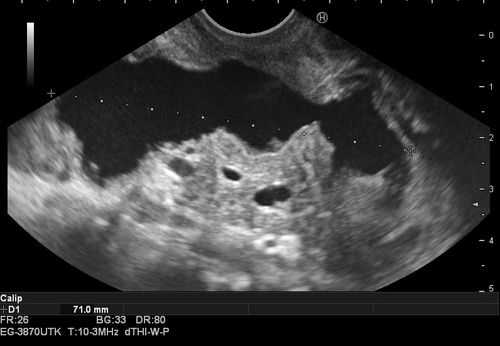

При эндосонографии (эндоУЗИ) в области головки поджелудочной железы визуализировано анэхогенное образование с четкими неровными контурами неправильной продольной формы, размерами 3,1х10 cм, прилежащее к воротной вене - постнекротическая киста с преимущественно внеорганным расположением (рис. 3).

Рис. 3